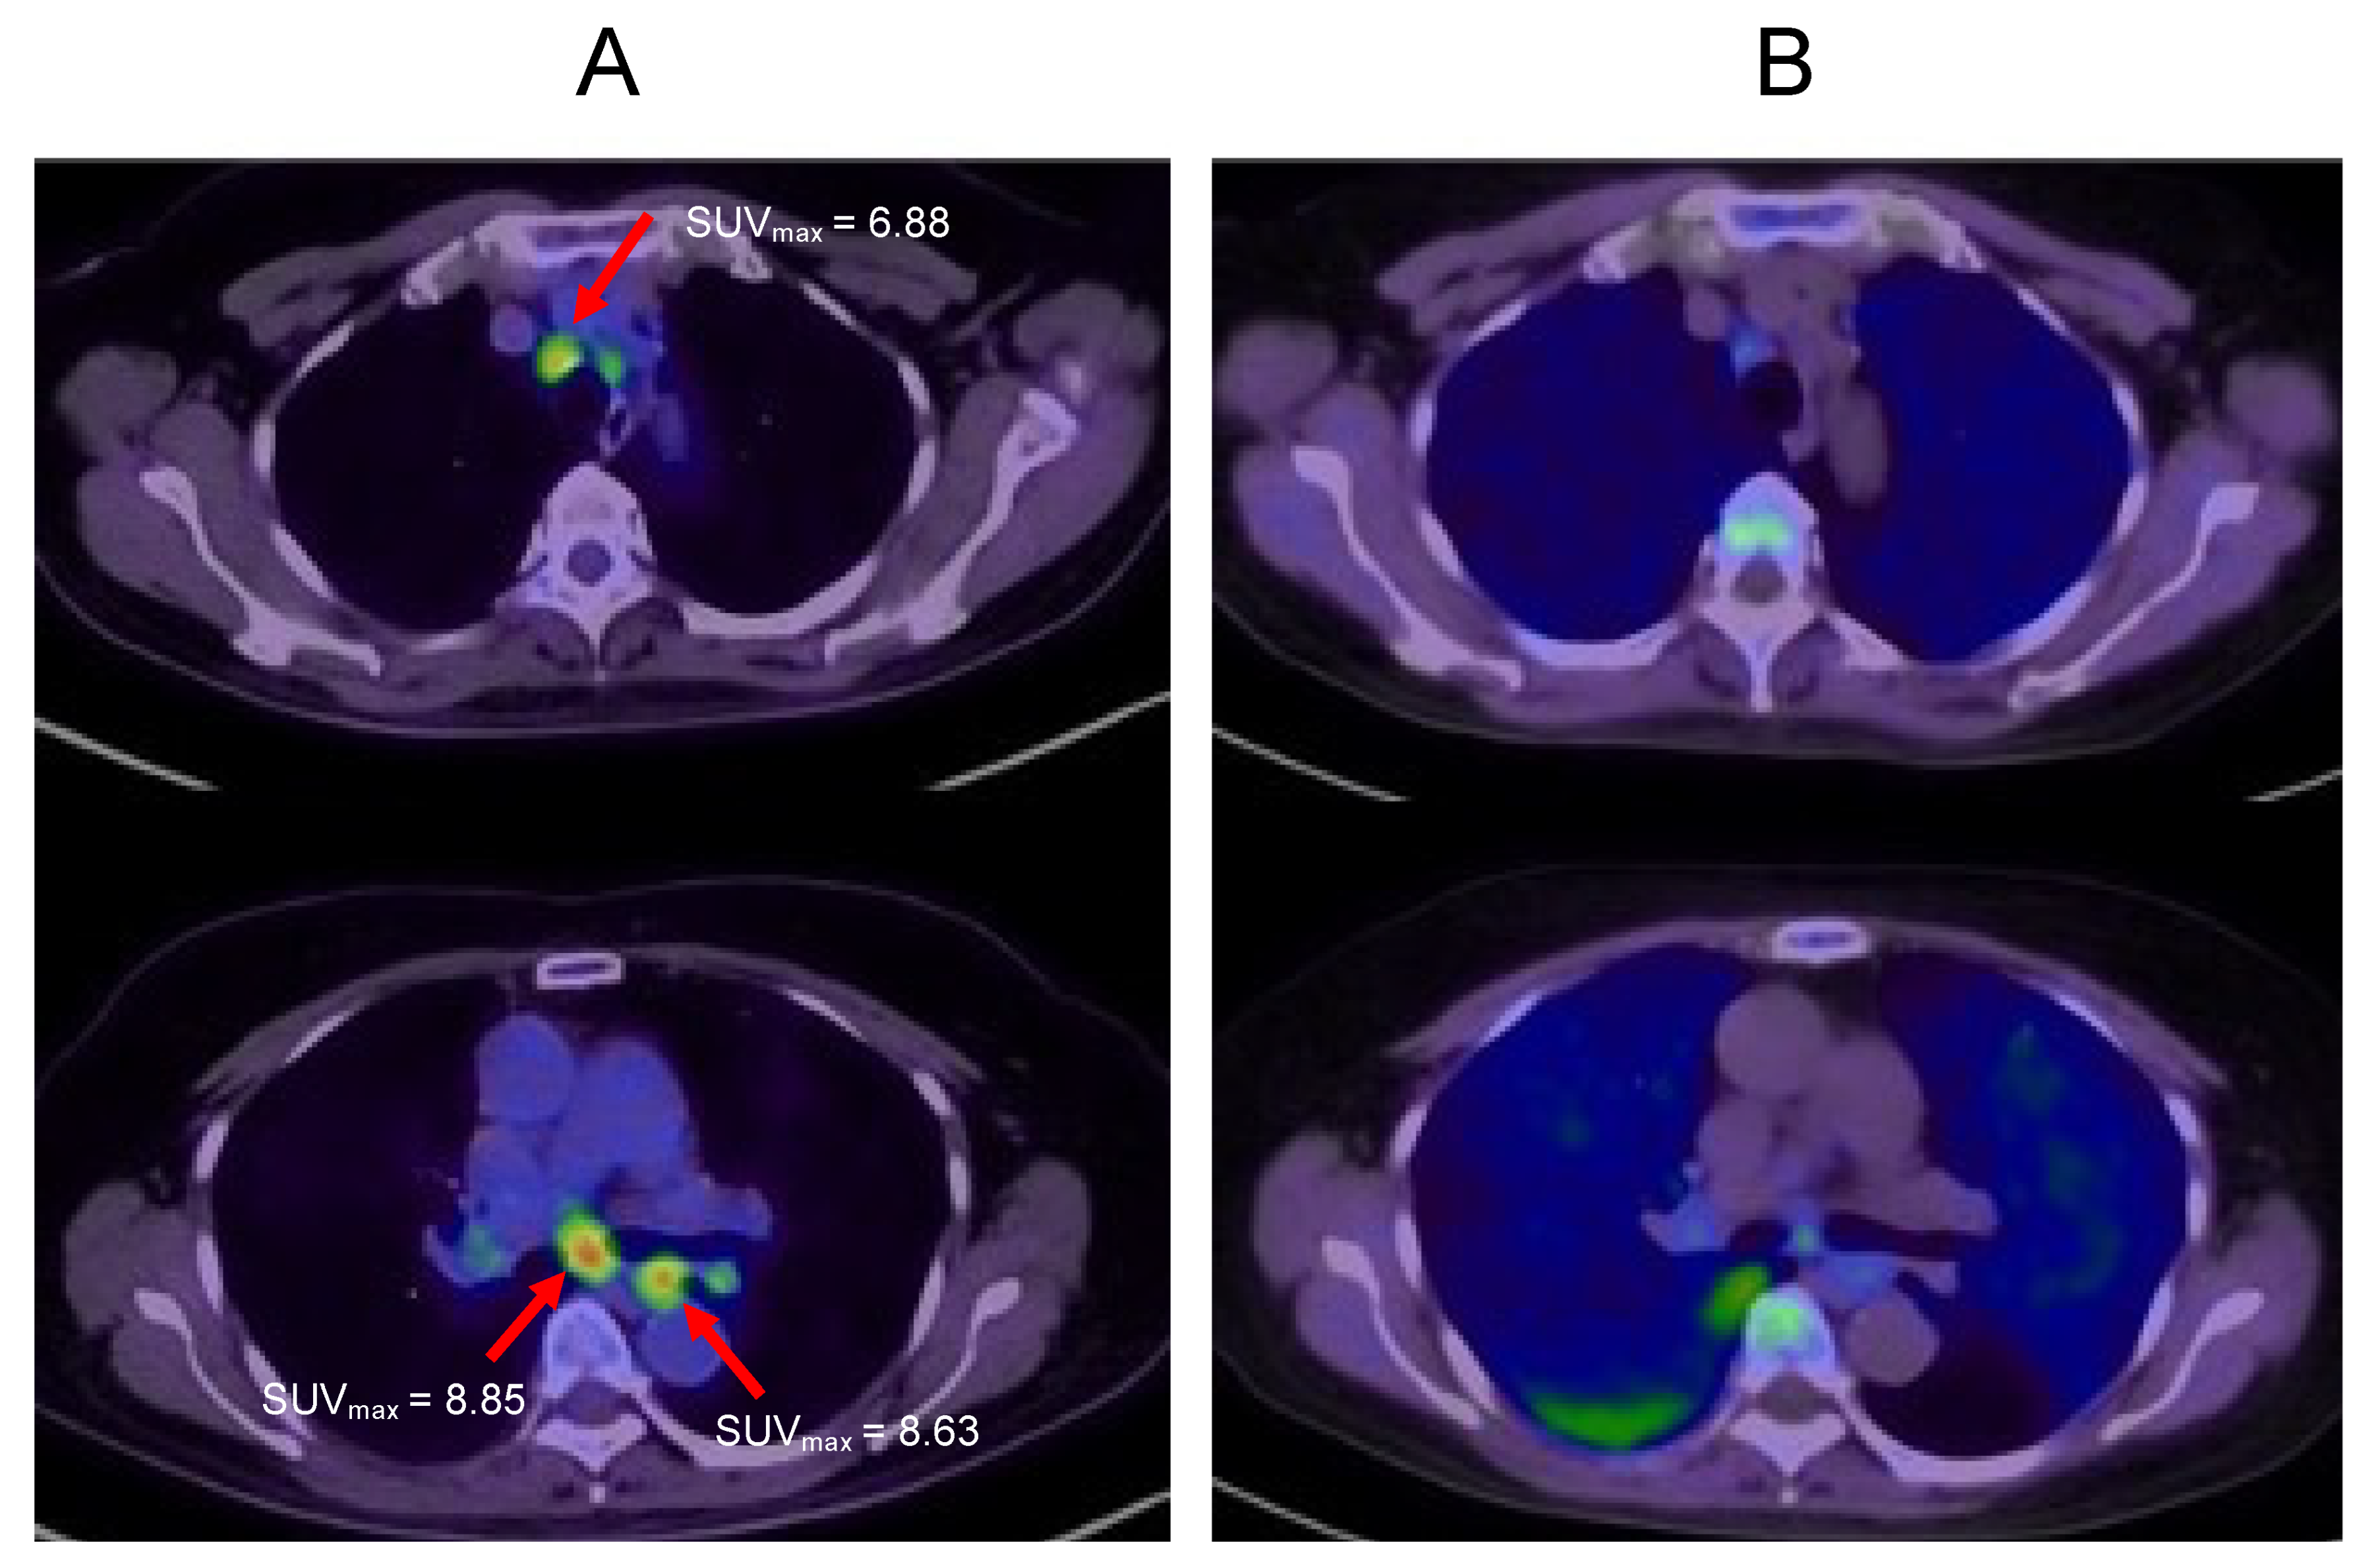

2.1. Case 1

2.2. Case 2